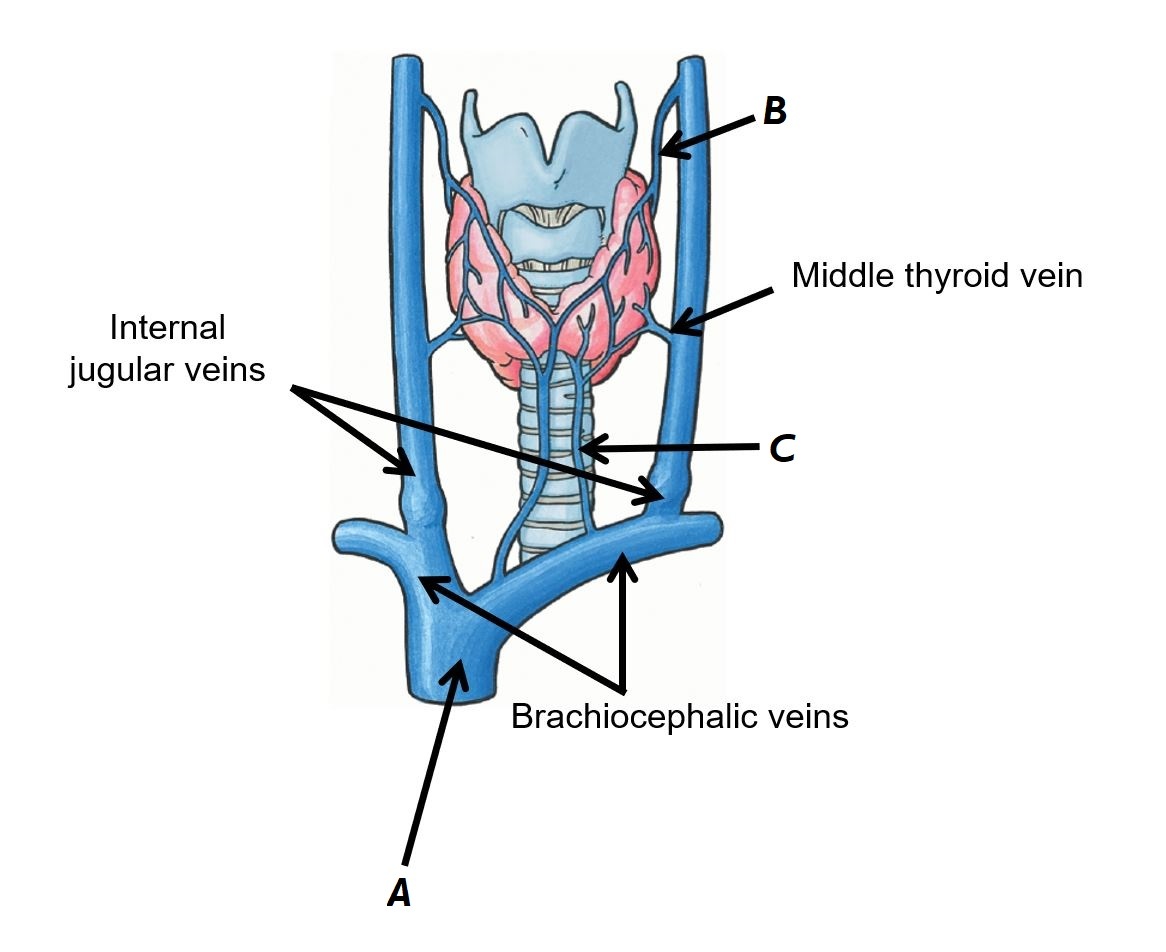

Name vessels A, B and C

A - Internal jugular veins

B - Brachiocephalic veins

C - Middle thyroid vein